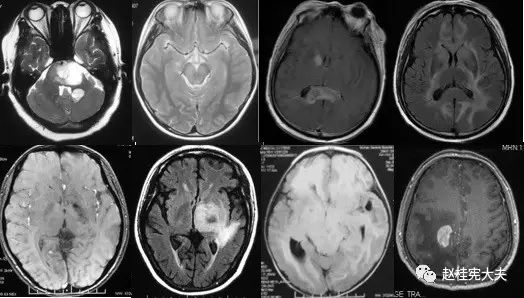

重要申明:以下每个部分会配磁共振图片,因疾病和影像之间存在同病异象、同像异病,为避免误导,图片不标注疾病,请各自鉴赏,另其中有部分图片来源于网络,有疑问可与本人联系。

H--hereditary,遗传

引起中枢神经系统病变的遗传性疾病可是种类繁多,主要指脑白质营养不良、脑小血管病等白质受累为主的病变。

如前者按发病机制可分为:溶酶体疾病(异染性脑白质营养不良、Fabry’s 病、Krabbe’s 病),过氧化物酶疾病(肾上腺脑白质营养不良(ALD)、肾上腺脊髓神经病(Adrenomyeloneuropathy))、线粒体疾病(MELAS、Leigh病)。按髓鞘病变病理过程种类分:异常髓鞘化:肾上腺脑白质营养不良、球形细胞脑白质营养不良、 染性脑白质营养不良;髓鞘化低下:佩梅氏病、Alexander病、白质消融性脑白质病;髓鞘囊性变性:Canavan病、空泡性脑白质病。

各种遗传性脑小血管病:如CADASIL、CARASIL、Fabry病及CAA、CAA相关性血管炎等等。

还有结节性硬化、各类NBIA(脑组织铁沉积神经变性病),脑肝肾综合征、线粒体脑病、LCC等。

S--stroke,卒中,即血管性

各种动脉性、静脉性血管病、静脉窦血栓形成、动脉夹层致脑梗塞、脑小血管病、脑动静脉畸形、CAA等,Moya-Moya也可出现脑实质的多发病灶,易被误诊为脱髓鞘。